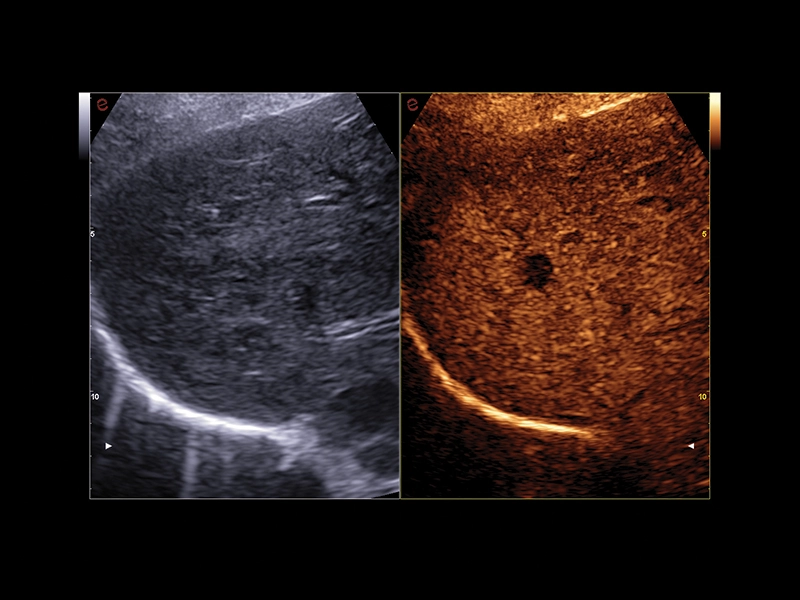

MyLab™C30 - MICROV-NEW

MyLab™C30 - MICROV-NEW